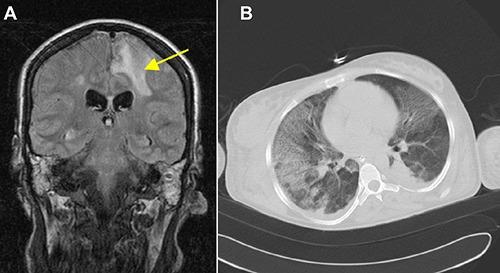

Necrotizing soft tissue infection of an extremity is a rare but life-threatening disease. The disease is an infection that involves the soft tissue layer and is characterized by rapidly spreading inflammation (especially of the fascial planes and the surrounding tissues) with a high mortality. Early diagnosis is essential for the outcome of the patients. Radical surgical debridement is the treatment of choice. The predisposing factors are immunosuppression, diabetes mellitus and drug abuse. This report presents a case of necrotizing fasciitis in the thigh, following an abscess of the sacro-iliac joint, as a rare complication in a young, immunosuppressed woman. The patient's history revealed intravenous drug abuse and hepatitis C. After immediate diagnosis by magnetic resonance imaging, radical surgical debridement was required and performed. Prior to soft tissue coverage with a split skin graft, five additional sequential debridements were necessary. During her hospital stay, the patient experienced further cerebral and pulmonary septic embolisms and an infection of the elbow. Six months after admission, the patient was discharged in good condition to a rehabilitation center. Necrotizing fasciitis is a life-threatening complication following an abscess of the sacro-iliac joint. Physicians must be vigilant to inflammatory signs and pain in immunosuppressed patients. An abscess of the sacro-iliac joint is rare, but complications of an untreated abscess can be fatal in these patients.